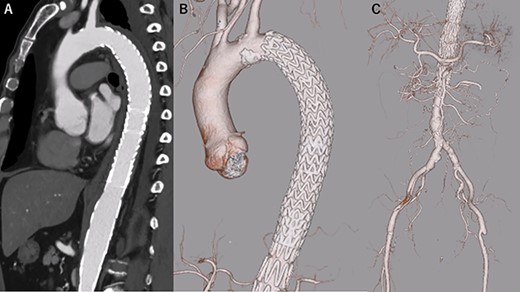

A 68-year-old man developed severe acute back pain and was diagnosed with acute type A aortic dissection with enhanced computed tomography (eCT) in the emergency department of our institute (Fig. 1A and B). The false lumen of the arch and ascending aorta was thrombosed (the maximum short diameter of the ascending aorta was 43.3 mm, the maximum diameter of the false lumen at the ascending aorta was 17.7 mm, Fig. 1C), and the primary entry was placed at the descending aorta. In addition, malperfusions were observed in the right renal artery and both iliac arteries (Fig. 1D). Therefore, we decided to perform TEVAR with the petticoat technique because of the rapid increase in true lumen blood flow.

eCT at diagnosis. (A): Sagittal view, (B) 3D reconstruction of the ascending and descending aorta, (C): Axial view of the ascending aorta and (D): 3D reconstruction of the abdominal aorta and iliac artery.

TEVAR was performed through the right femoral artery (rFA) with cut-down. Pulsation was not observed; therefore, we confirmed that the rFA was not dissected using echography from the surface. A 5Fr sheath (Medikit Super Sheath, Medikit, Tokyo, Japan) and 0.035-inch guidewire (Radifocus, Terumo, Tokyo, Japan) were inserted carefully, and we confirmed it in the true lumen using transesophageal echography (TEE) during the operation (Fig. 2A). Subsequently, a 5Fr pigtail catheter (Medikit, Tokyo, Japan) was inserted, and the guidewire was changed to a stiff wire (Lunderquist extra-stiff guidewire, Cook, Bloomington, IN, USA). Then, a 20 Fr Dryseal sheath (WL Gore and Associates, Flagstaff, AZ) was inserted. Through the sheath, we deployed Conformable TAG (26 mm × 100 mm; WL Gore and Associates, Flagstaff, AZ) at the descending aorta. Next, we deployed Conformable TAG (26 mm × 150 mm; WL Gore and Associates, Flagstaff, AZ) just distal to the left subclavian artery to the first stent graft with sufficient overlap. At this point, we observed expansion of the true lumen with TEE (Fig. 2B). Finally, we placed the Zenith Dissection Bare stent (36 mm × 164 mm; Cook, Bloomington, IN) at the distal end of the second stent graft with one stent overlap (Fig. 3). We confirmed the improvement of malperfusion and no access trouble.

The postoperative course was uneventful, and he was discharged 14 days postoperatively. Rapid aortic remodeling was observed with eCT at 1 and 11 days postoperatively (Fig. 4). Right iliac artery dissection did not impede blood flow and no other complications such as stent-induced new entry (SINE) were observed (Fig. 5). We strictly followed up the false lumen and iliac dissection.